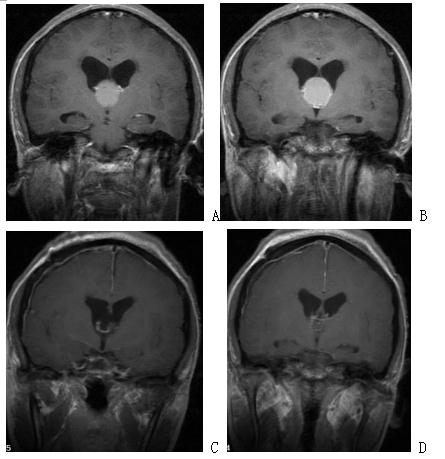

图2. A、B手术前增强磁共振,提示复发巨大全斜坡脊索瘤;C、D内镜经鼻手术后增强磁共振,提示肿瘤全切。